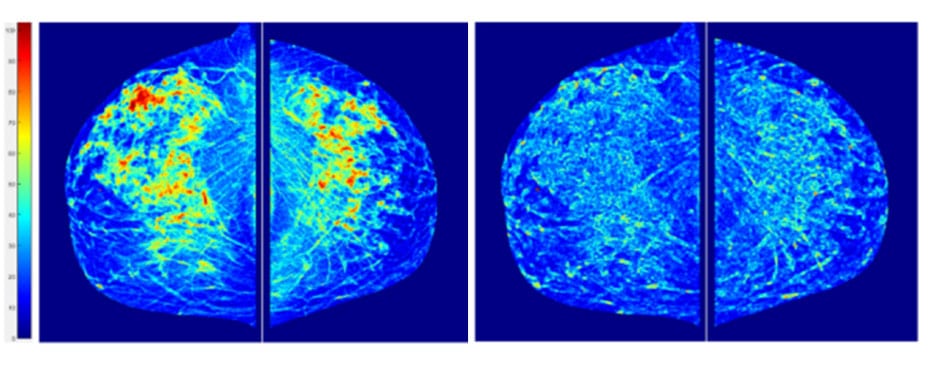

近20年来,在计算机数字图像处理和机器学习技术飞速发展帮助下,用于图像、分类诊断乳腺癌技术大有改善自20世纪90年代计算机辅助诊断技术开发初期以来,匹兹堡大学和俄克拉荷马大学的BinZheng教授就致力于研究评估自身能力从确认从数位乳房X线图到使用MRI评估乳房肿瘤对化疗响应